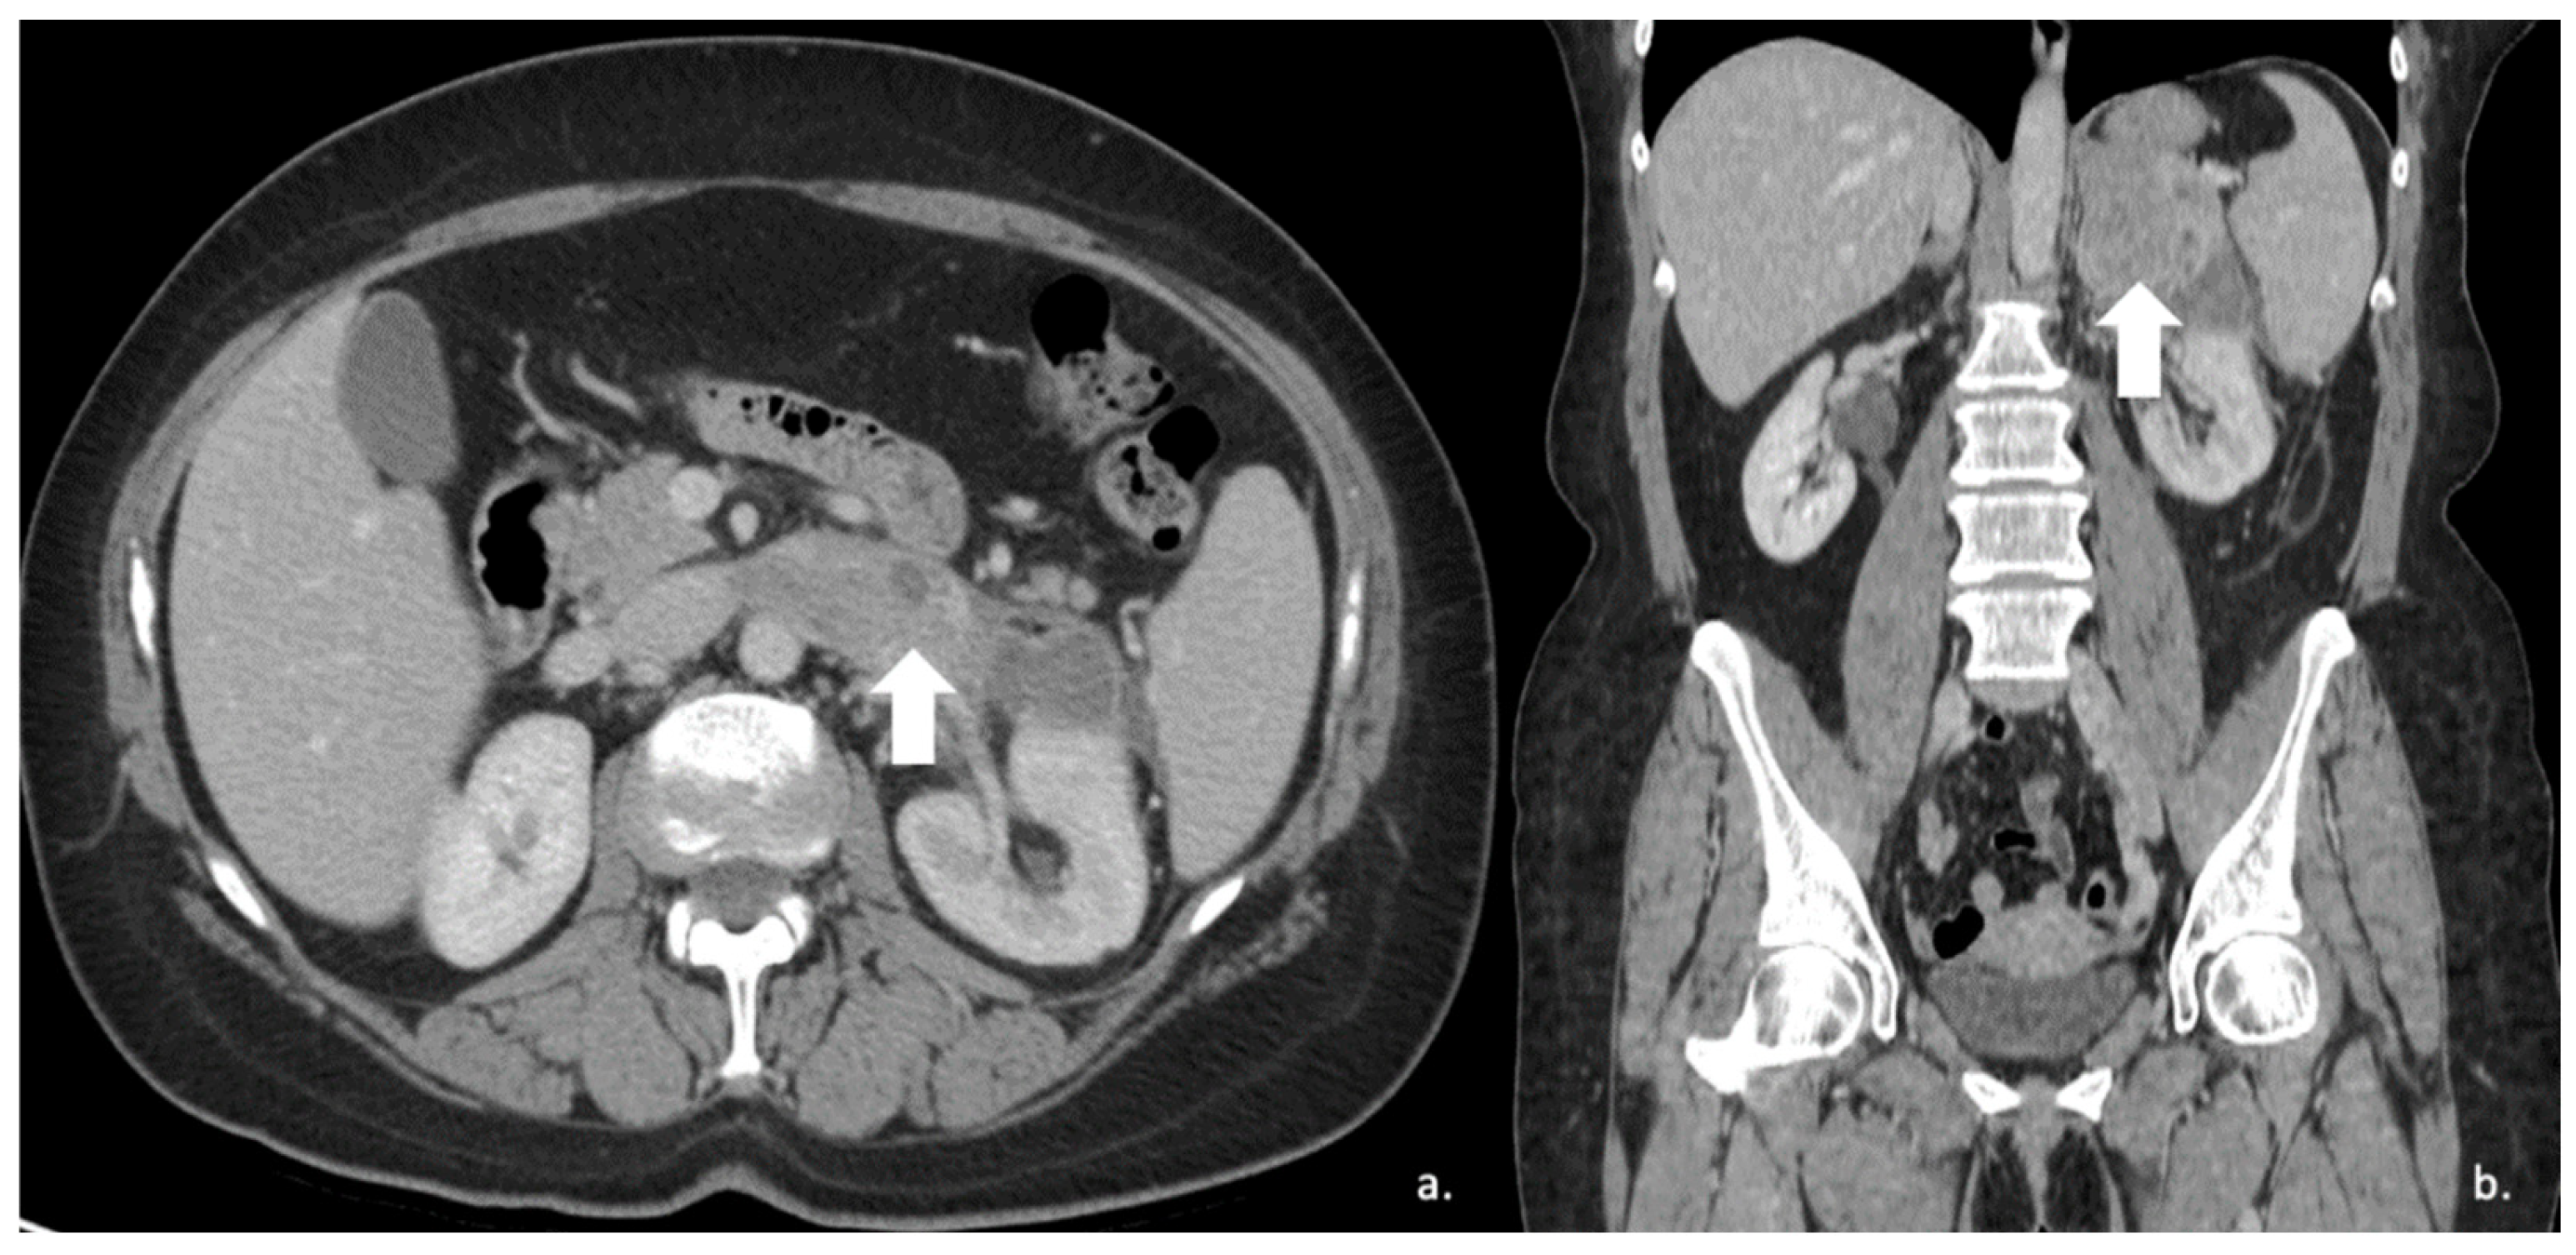

Figure 3.

60-year-old woman with history of breast cancer and adrenal metastasis. Left adrenal mass with inhomogeneous enhancement (arrow) on CT portal phase in axial (A) and coronal (B) planes, and positive PET (C).